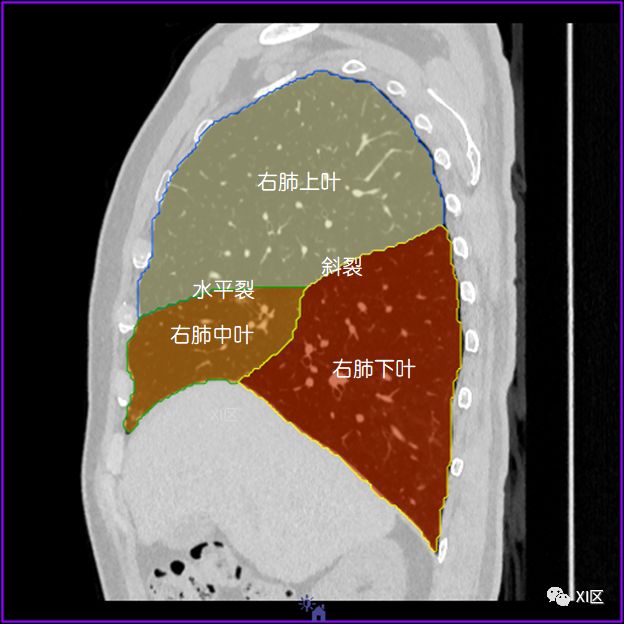

左肺借斜裂成上、下两叶;右肺借斜裂和水平裂成上、中和下叶三叶。

矢状位

肺表面重建显示叶间裂和肺的分叶

透视图显示肺的叶间裂和肺的分叶

肺的分叶